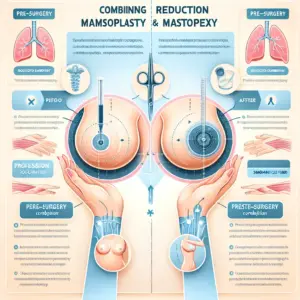

Qual a Melhor Cirurgia para Levantar as Mamas? Comparação Entre Técnicas e Resultados

A melhor cirurgia para levantar as mamas varia conforme o grau de ptose, volume e pele, com técnicas específicas para cada caso. Avaliação médica personalizada é essencial para resultados naturais e satisfatórios.